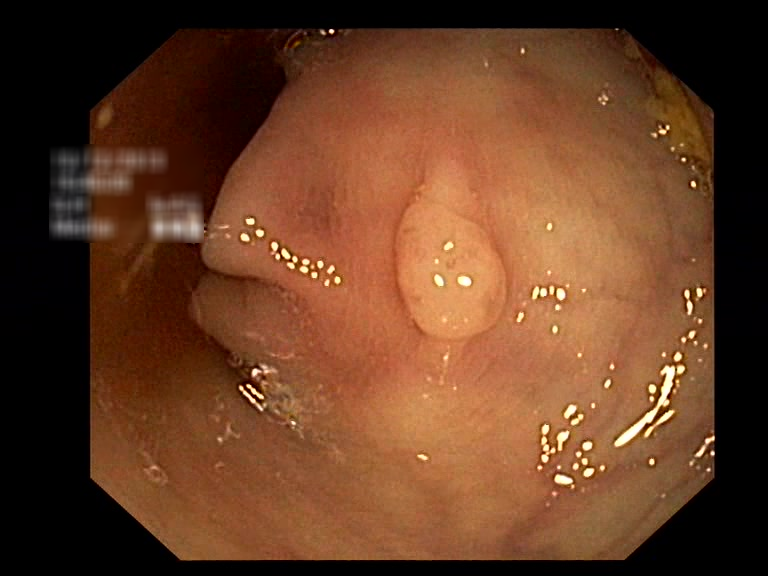

| Lesion | White Light Frame | NBI Frame | White Light Video | NBI Video | Camera Calibration |

| serrated_01 |  |

|

WL.mp4 | NBI.mp4 | cam.xml |